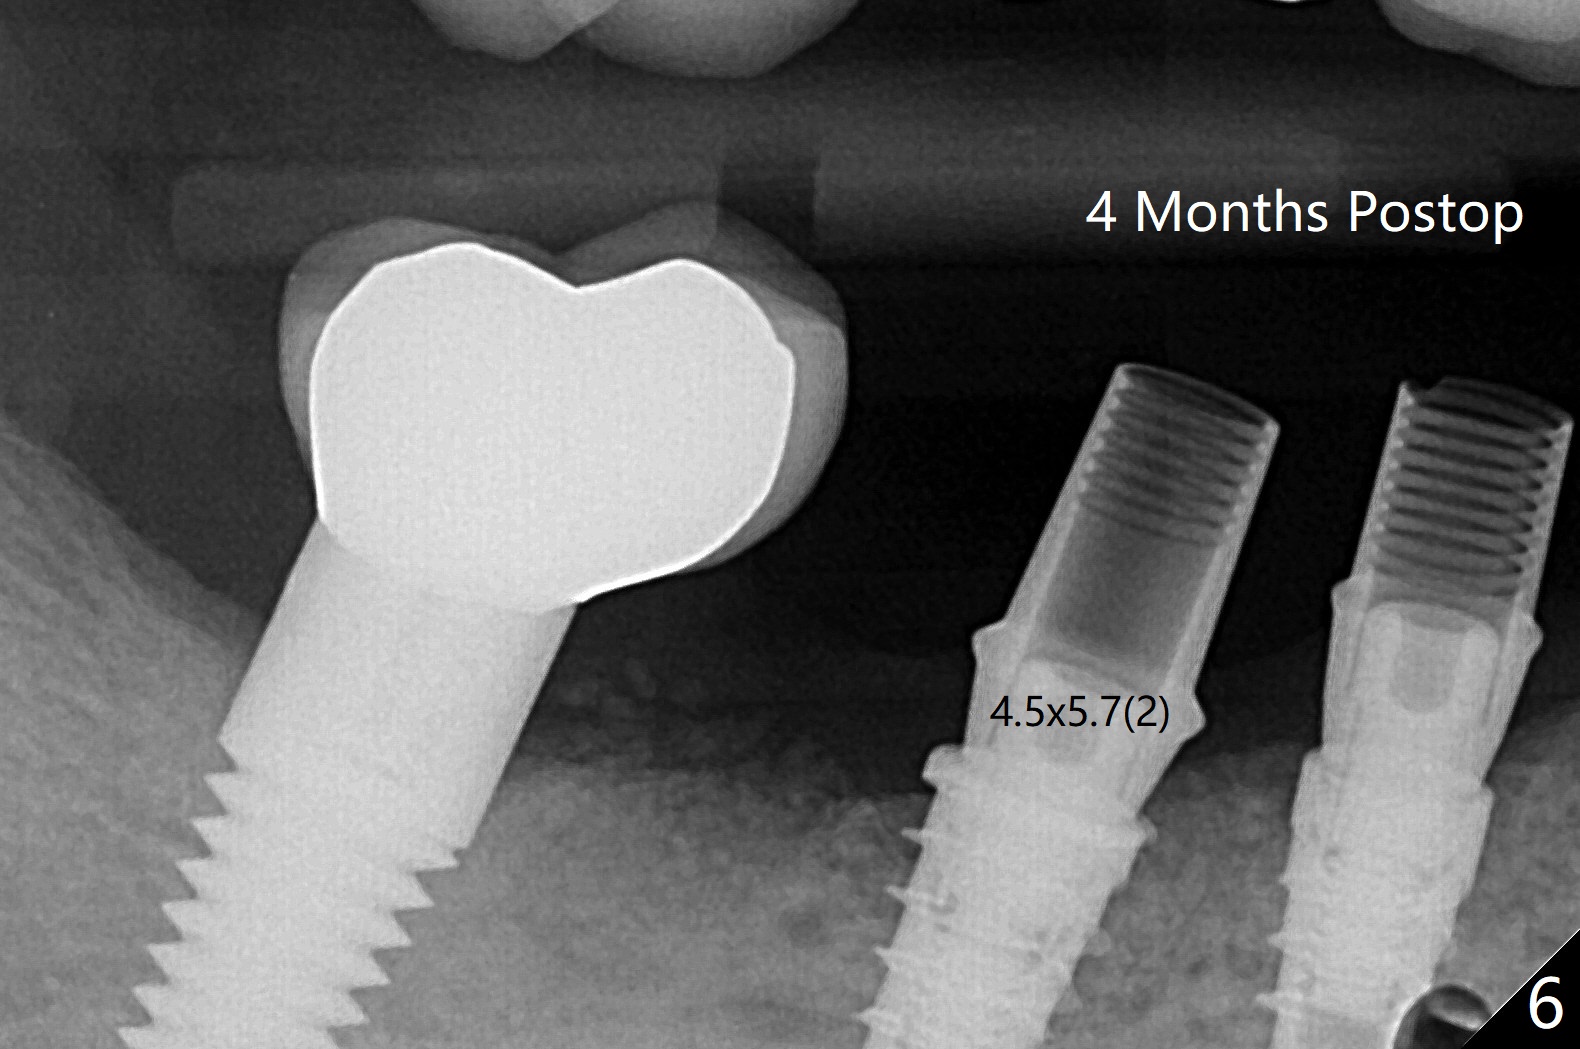

右下5,6植体植入后,取下导板,发现两者都植入不够深,放回导板,5植体植入深点(35Ncm),但是6植体与植牙工具通过导板接不上,正好取出导板,徒手旋紧,不幸的是植体往近中移位(图一:空箭头,远离中隔(S)),稳定性好像降低,不适合即刻修复,放置愈合螺帽后,大量植入粘性骨粉,包括进入7近中(短箭头,事先需要往上分离龈乳头),覆盖PRF膜,PGA缝线,利用5基台,固定树脂敷料。术后5个星期,撤除树脂敷料,虽然愈合螺帽暴露,周围牙龈健康,并含有骨粉(图二)。术后两个月植体基本被覆盖(图三),术后3.5个月植体完全覆盖,切开前根尖片显示植体平台与牙槽嵴平齐(图四),术中证实。5基台好像没有就位(图四(可能拍摄角度不佳)),将基台平面从远中旋转至颊侧,就位仿佛改善(图五)。术后四个月6放置基台后(图六),制作连体5,6牙冠,垫高(打开咬合),近中衬里,推4,关闭3,4之间间隙(图三)。6植体远中第一个螺纹好像暴露。